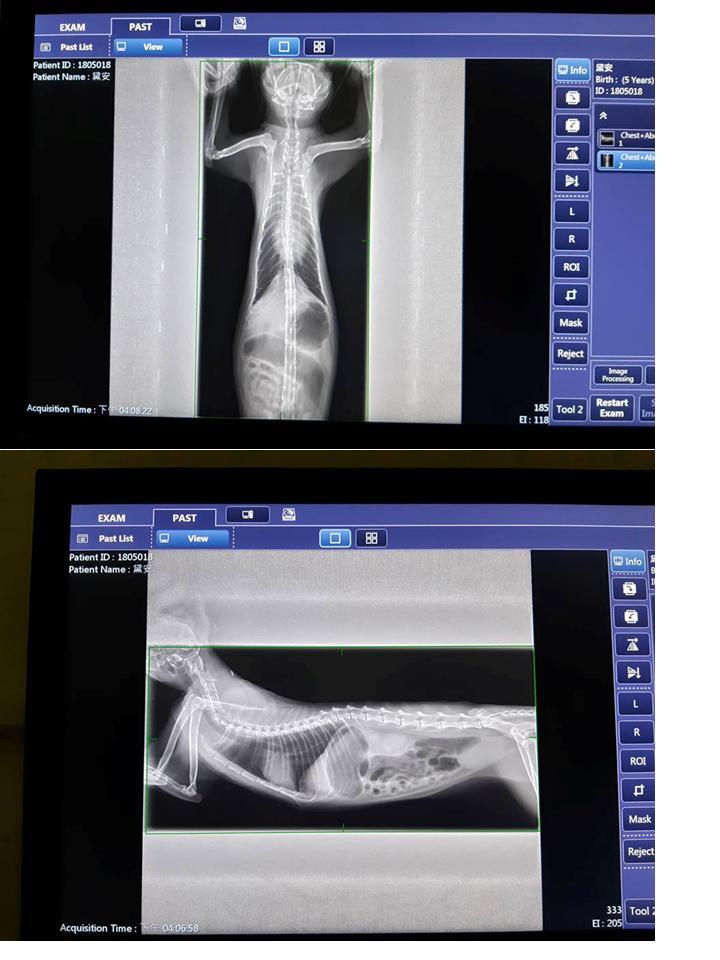

在今年5/18,照護員發現黛安有流鼻水、淚眼、無食慾等情況,於是在5/22將她接至台北澄諾醫院接受醫療,醫師為黛安進行血球及血液生化套組檢查、胰臟炎檢測、照X光,診斷黛安是上呼吸道感染,血檢顯示白血球過高,須住院施打靜脈注射、氣霧、為期五週的抗生素治療,並有進行耳疥治療。

黛安自5/22入院至6/7情況較為穩定可以出院,仍需要每週回診檢查追蹤,且因

住院期間,醫師發現她左上顎第四前臼齒牙周病,牙齒搖動,為了避免日後口腔問題再次影響黛安健康,於是在休養幾周後,狀況較為穩定時,再安排黛安於6/28進行拔牙洗牙的手術,請大家幫忙黛安妹妹這期間的醫療費用。

1.醫師說明5/22-6/7的情形

1. BW2.76(5/22)>>3.11kg(6/19)

2. 上呼吸道感染、白血球增多,抗生素治療5周。

3. 懷疑耳疥感染或是耳疥感染後耳發炎,住院及門診使用耳疥耳藥,6/6點寵愛。

4 左上顎第四前臼齒牙周病,牙齒搖動,建議可考慮進行牙周治療。